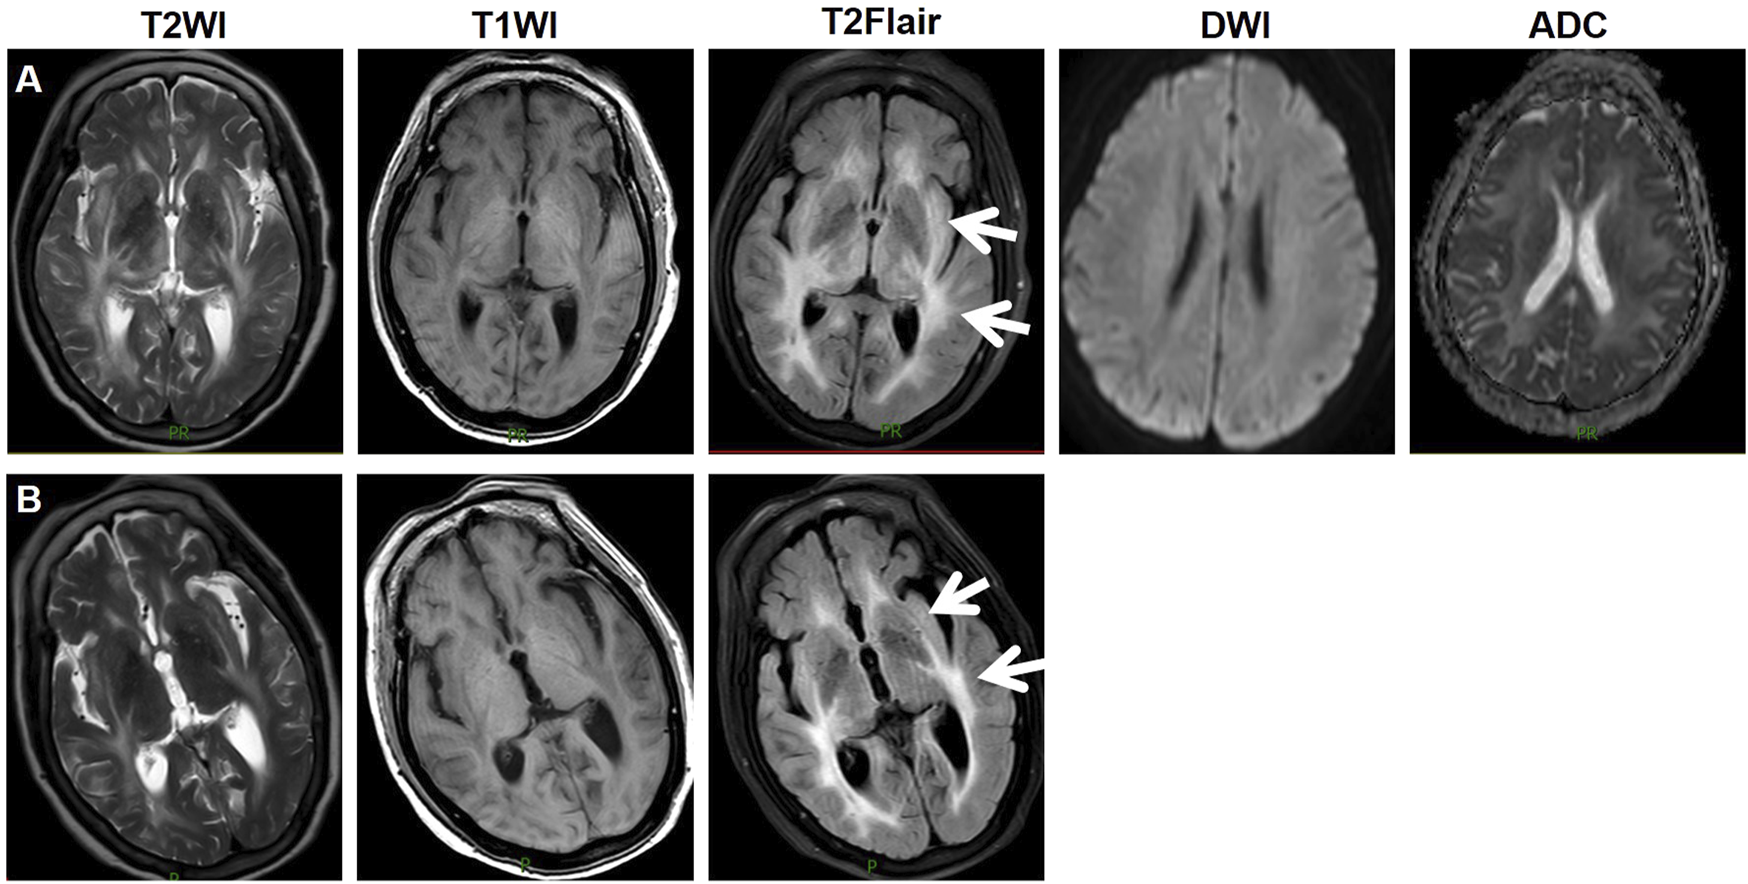

During treatment, CT and magnetic resonance imaging (MRI) identified a hepatic metastatic tumor on 15 May 2023, indicating disease progression. However, the patient chose not to undergo TACE, and on 1 July 2023, lenvatinib 8 mg QD was initiated for salvage therapy. Initially, the patient did not experience any adverse reactions. Lenvatinib therapy was continued due to unresectable HCC. She had been well until 1 week prior when she started experiencing confusion, difficulty identifying familiar people, and a longer sleep duration. Three days ago, the patient experienced a consciousness disorder, including progressive deterioration of consciousness and double incontinence. Furthermore, she had a blood pressure (BP) of 204/120 mmHg, despite having no history of hypertension, and suddenly developed a severe headache. The patient was admitted on 29 August 2023, due to abnormal mental behavior. During the neurological examination, the patient entered a state of lethargy. Furthermore, the patient had muscle strength and normal symmetrical reflexes. CT, MRI, and magnetic resonance angiography images revealed no signs of intracranial hemorrhage or infarction. Biochemical testing, including complete blood cell count, blood chemistry, coagulation, and kidney function tests did not detect any significant abnormalities, with an estimated glomerular filtration rate (eGFR) of 99.186 mL/min. The patient exhibited mild hepatic dysfunction characterized by predominantly unconjugated hyperbilirubinemia (total bilirubin: 34.8 μmol/L; direct bilirubin: 5.6 μmol/L; indirect bilirubin: 24.9 μmol/L). Notably, hepatocellular integrity was preserved, as evidenced by normal transaminase levels (aspartate aminotransferase: 28 U/L; alanine aminotransferase: 32 U/L) with normal serum ammonia levels (23 μmol/L). Immunological evaluation revealed weakly positive autoimmune markers (anti-histone antibody: 1:50; antinuclear antibody: 1:100, speckled pattern), while comprehensive serological testing excluded antiphospholipid syndrome (negative for lupus anticoagulant, anti-cardiolipin, and anti-β2-glycoprotein I antibodies) and systemic vasculitis (negative for anti-neutrophil cytoplasmic antibodies and anti-endothelial cell antibodies). On August 30, an MRI revealed bilaterally distributed hyperintensity of the white matter in the periventricular and basal ganglia on T2 images, and fluid-attenuated inversion recovery (FLAIR) images. However, restricted diffusion was not observed on diffusion-weighted imaging or the apparent diffusion coefficient (Figure 1A). These observations indicated vasogenic edema, leading to suspicion of Fazekas grade 3 PRES. Cerebrospinal fluid (CSF) analysis revealed normal glucose levels and cell counts, along with increased albumin (2432 mg/L, normal range: 150–450 mg/L). Comprehensive relevant diagnostic testing, including tests for metabolic, demyelinating, vascular, and tumoral conditions, ruled out any relevant issue. Drug toxicity could not be excluded due to progressive encephalopathy. Therefore, lenvatinib was immediately discontinued, and BP was controlled using intravenous urapidil at 130–140/80–90 mmHg. After 5 days, her neurological symptoms gradually improved. On September 4, a follow-up MRI reexamination indicated a slight reduction in the signal abnormality in the bilateral white matter (Figure 1B). The patient was discharged after 7 days of admission.

FIGURE 1

Imaging manifestations of the patient. On August 30, an MRI revealed bilaterally distributed hyperintensity of the white matter in the periventricular and basal ganglia on T2 images, and fluid-attenuated inversion recovery (FLAIR) images. Restricted diffusion was not observed on diffusion-weighted imaging or the apparent diffusion coefficient (A). On September 4, a follow-up MRI reexamination indicated a slight reduction in the signal abnormality in the bilateral white matter (B). Abbreviations: T2WI, T2 weighted imaging; T1WI, T1 weighted imaging; T2Flair, T2 fluid attenuated inversion recovery; DWI, diffusion-weighted imaging; ADC, apparent diffusion coefficient.